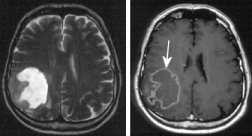

El cerebro Alzheimer

perdió una grande parte de su substancia cuando

en comparación a un cerebro sano. El mercurio

esencialmente es una parte de ese proceso. El cerebro Alzheimer perdió una grande parte de su substancia cuando en comparación a un cerebro sano. El mercurio esencialmente es una parte de ese proceso.

En el año 1907 la enfermedad Alzheimer fue descrito la primera vez por el neurólogo Alois Alzheimer de Breslau (Wrozlaw) y afecta mayormente mujeres entre 55 y 65 años.

Para la grande mayoría de los casos de reducción de la fuerza mental (demencia, reducción o pérdida de todos los procesos mentales) es la enfermedad Alzheimer que es responsable. Normalmente va seguir la muerte después de 10 años (p.41).

La medicina convencional no conoce la causa de esa enfermedad; antes una carga de aluminio fue considerada como causa, pero eso mayormente es un factor de segunda prioridad. Más o menos 5% de los casos Alzheimer son provocados genéticamente (mutaciones de cromosomas 14, 19, 21). Durante ese enfermedad se depositan proteínas enfermas en el cerebro (plaque senil por amiloida beta) (p.41).

Investigación de cerebros de personas muertas respecto a oligoelementos

Fueron comparados dos grupos. Un grupo fueron personas que habían muerto por la enfermedad Alzheimer, y un otro grupo fueron todas las otras pacientes. El nivel de mercurio en el tejido cerebral de los pacientes Alzheimer fue aumentado, en las regiones cerebrales degeneradas por la enfermedad Alzheimer hasta cuatro veces más (p.41).